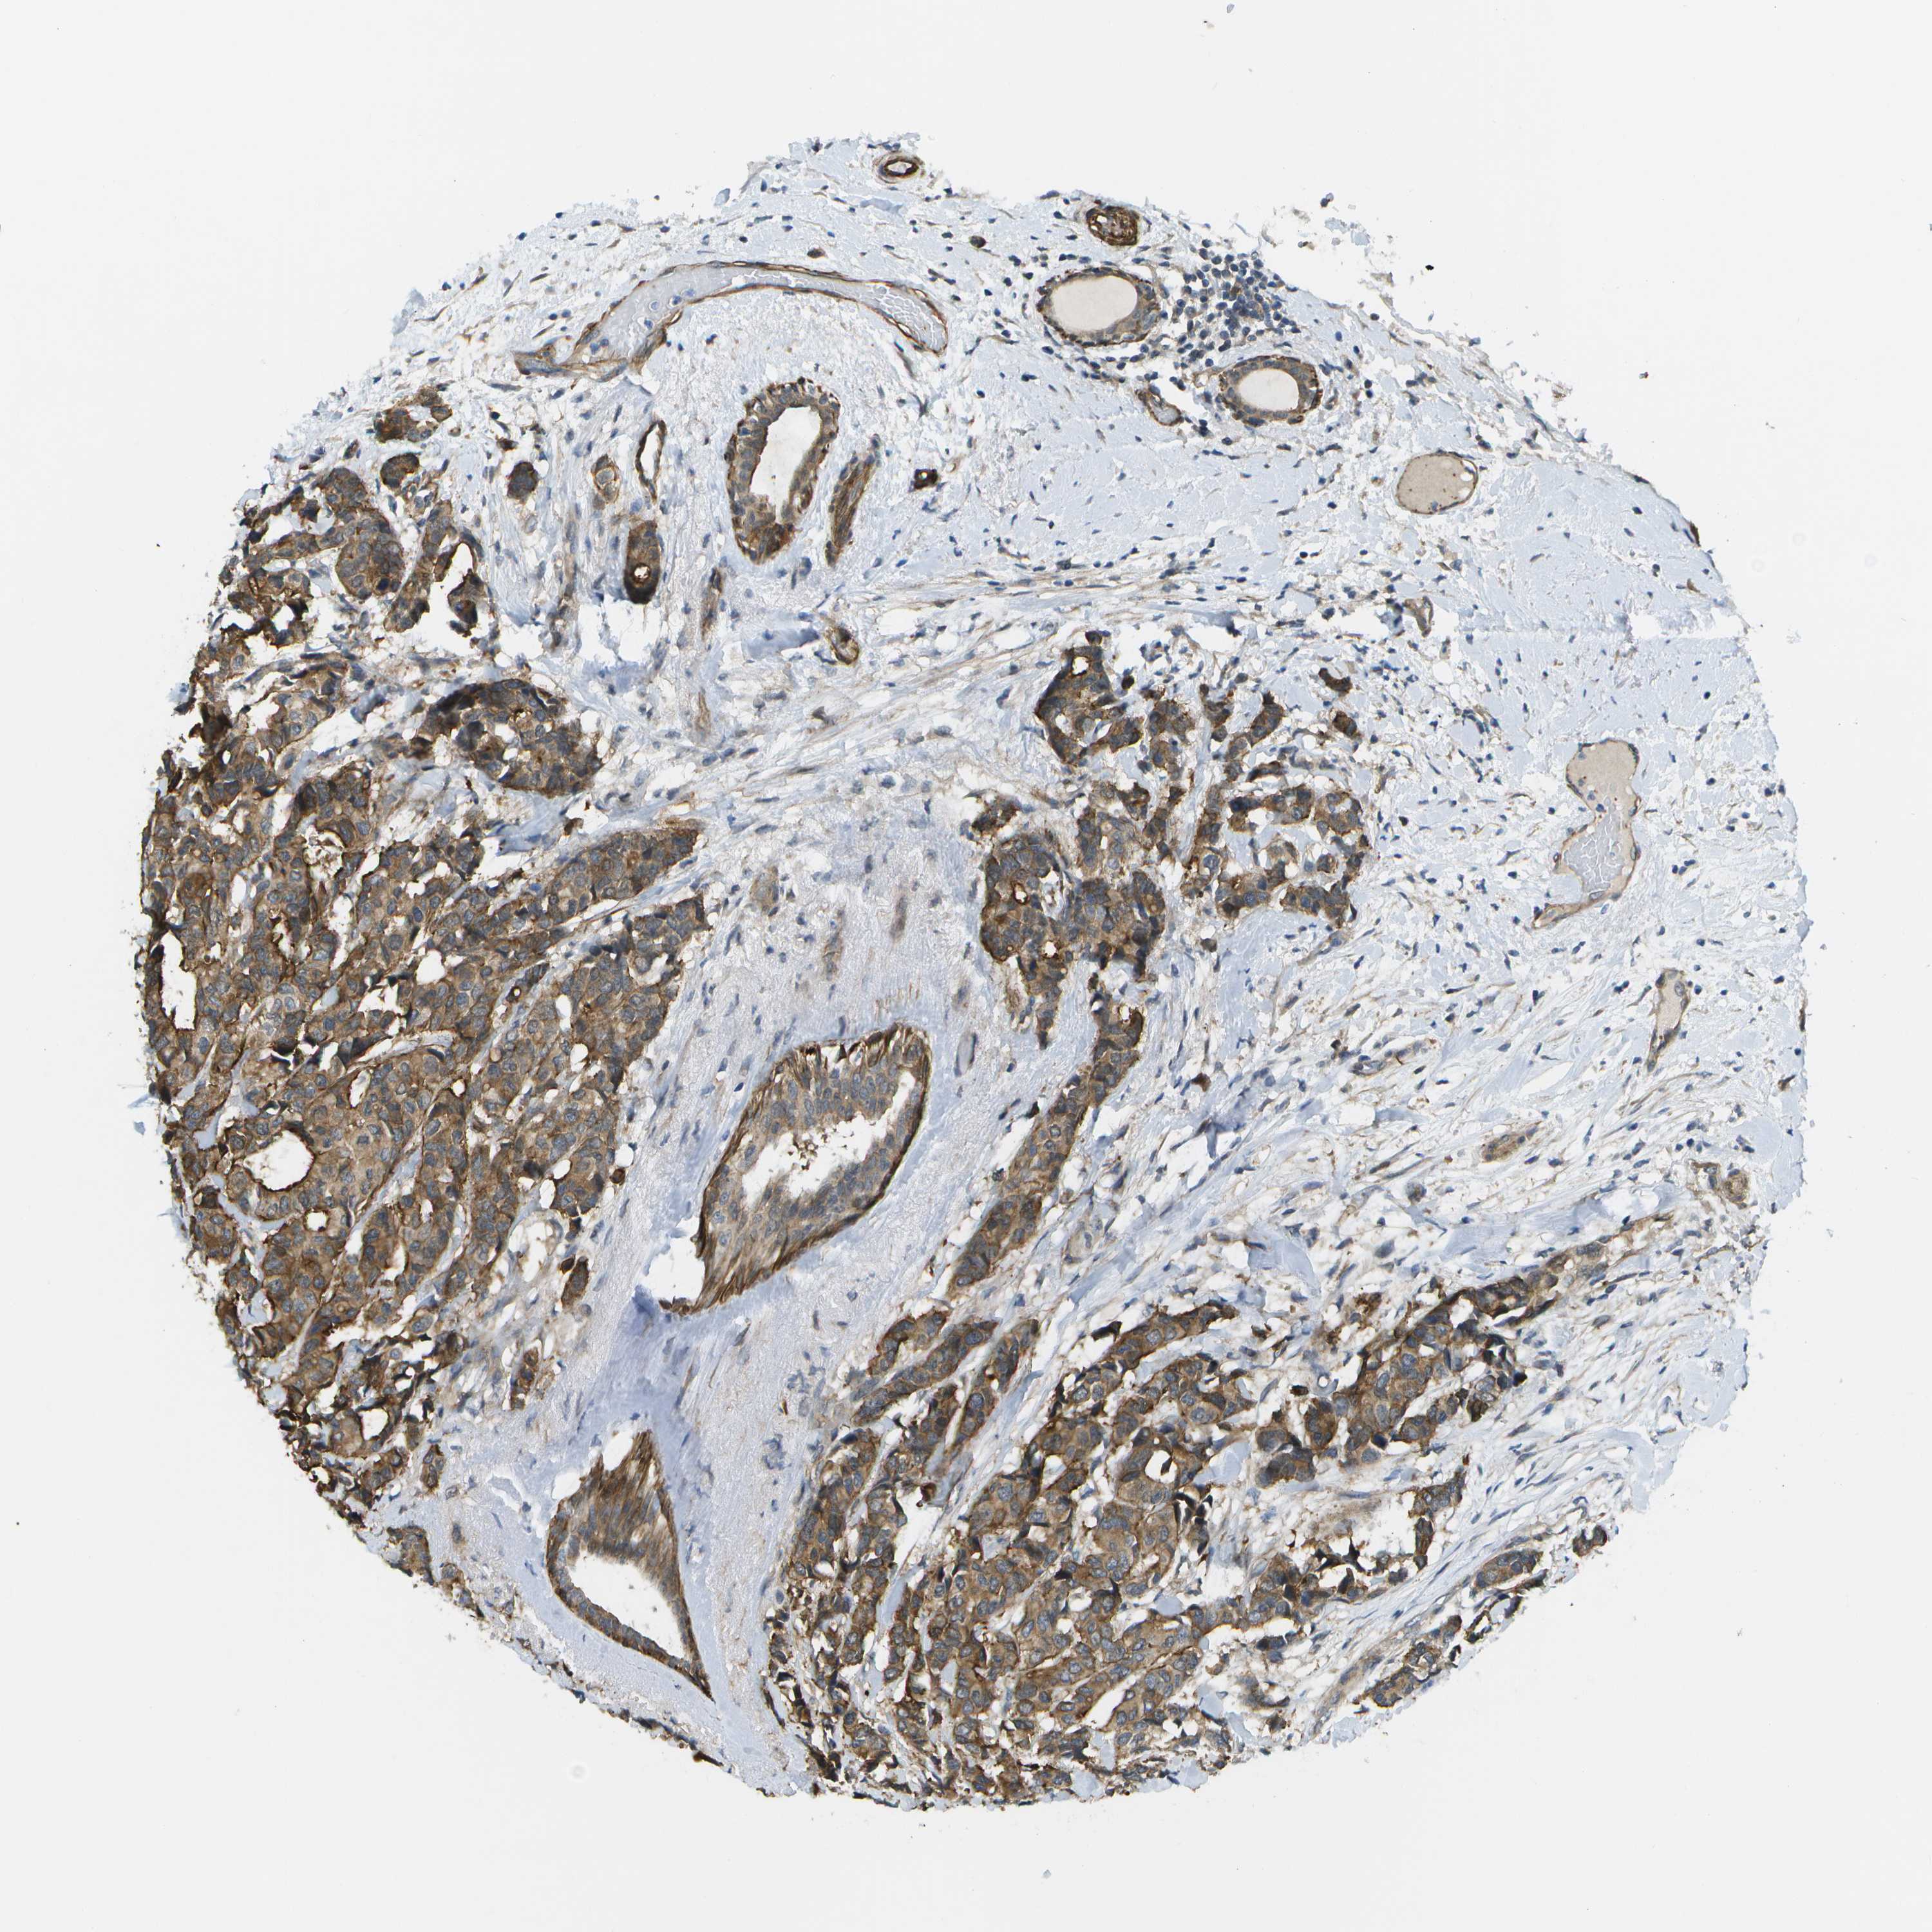

BRCA TCGA BRCA VALIDATION PROTEIN EXPRESSION

ANTIBODIES

AND

VALIDATION